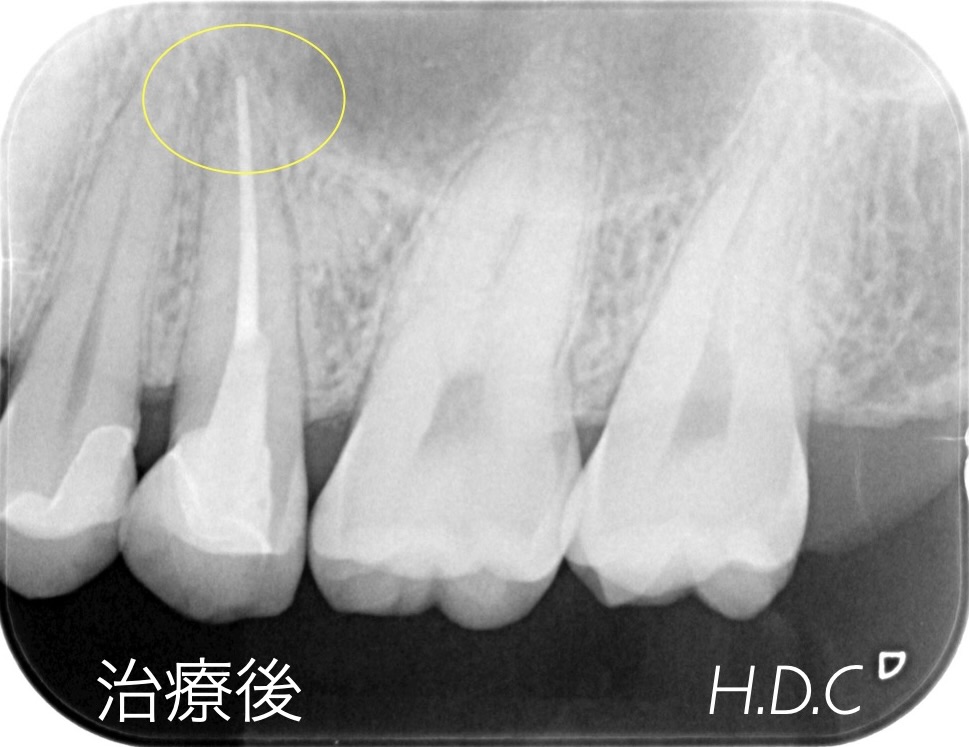

根管治療例③

- 年齢・性別

- 30代 男性

- 主訴

- 右上の前歯の歯肉が腫れた。

- 診断名

- 根尖性歯周炎

- 治療内容

- 根管治療後、コンポジットレジンにて修復治療を行いました。

- 治療期間

- 約3ヶ月

- 治療費用

- 保険診療

- リスク

- 根尖性歯周炎の再発、歯根破折、コンポジットレジンの破折など